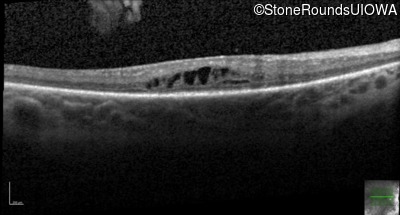

Optical Coherence Tomography - Right - 20/80 +2

Exemplar / OCT Stack